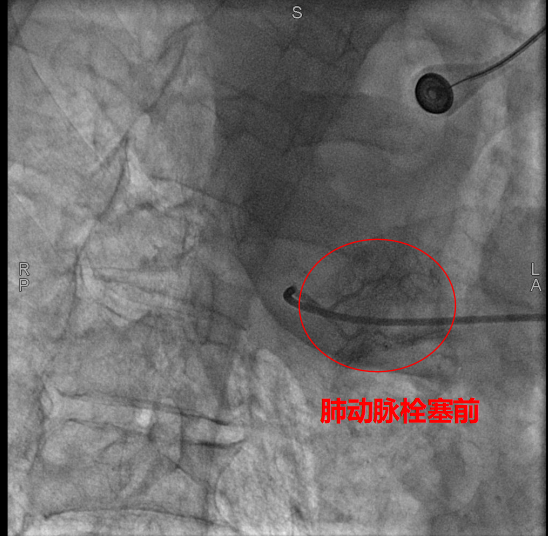

术中,数字减影血管造影(DSA)显示患者右侧支气管动脉及胸廓内动脉增粗紊乱,末梢血管可见造影剂点状外溢,明确为主要出血责任血管。团队采用400 µm栓塞微球及560–710 µm明胶海绵颗粒,对出血动脉远端实施精准栓塞,实现“末梢血管封堵”;同时,对肺动脉分支血栓相关区域也予以栓塞处理,以全面控制咯血来源。术后造影确认出血完全停止,患者安返病房后未再咯血,胸闷、气促等症状显著缓解。